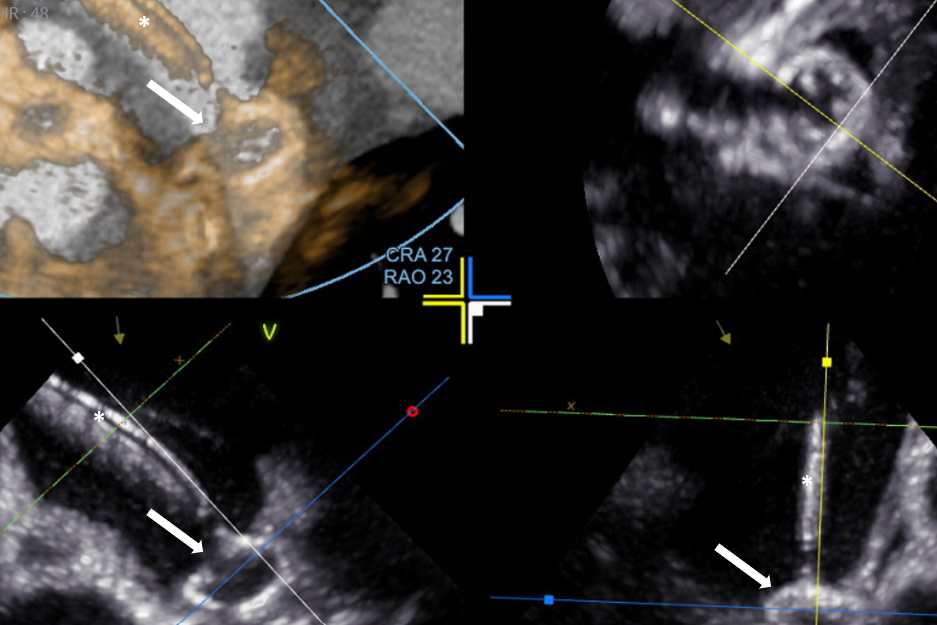

Kwalifikacja do zabiegów prowadzona jest na Oddziale Chorób Strukturalnych Serca, którego koordynatorem jest prof. Marcin Fijałkowski z I Katedry i Kliniki Kardiologii GUMed. Kluczową rolę w planowaniu zabiegów odgrywa echokardiografia przezprzełykowa i tomografia komputerowa serca. Szczegółową analizą obrazów tomografii komputerowej zajmuje się prof. Edyta Szurowska kierująca II Zakładem Radiologii GUMed oraz dr Dorota Kulawiak-Gałąska z Zakładu Radiologii naszego Uniwersytetu.

Skopia rentgenowska – okluder w uszku lewego przedsionka przed odłączeniem od systemu dostawczego